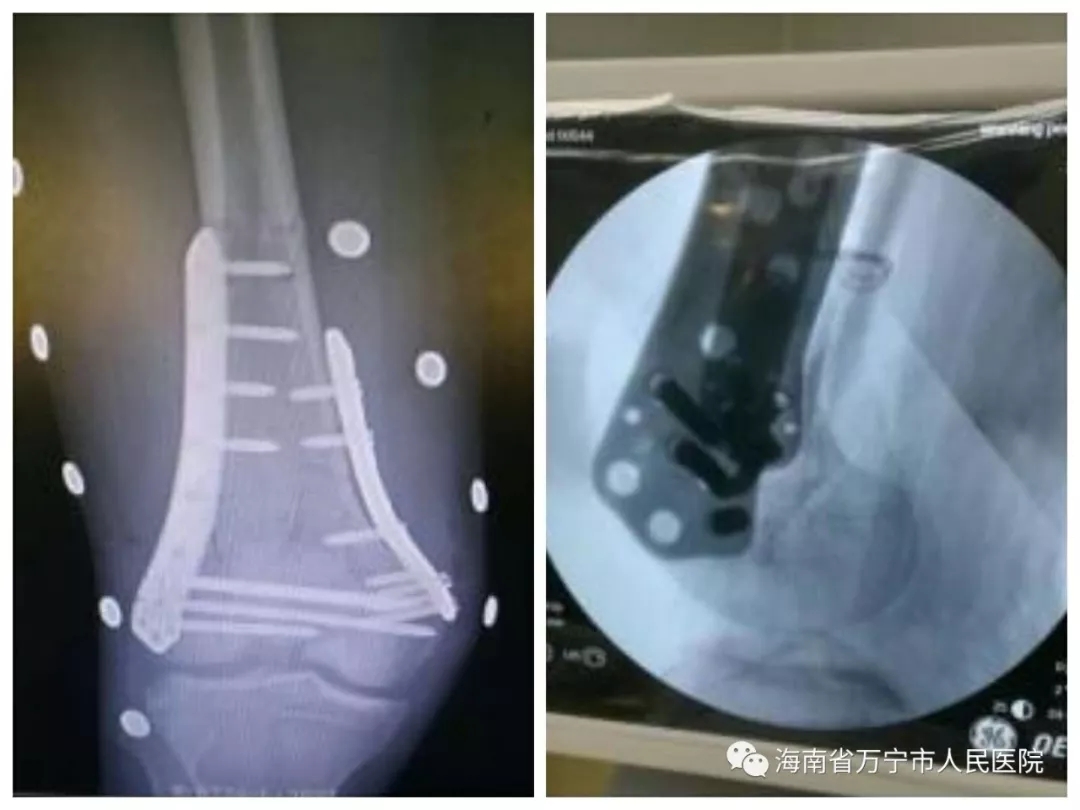

近日,万宁市人民医院骨科成功为一例开放性、粉碎性股骨髁间骨折患者进行手术治疗,该患者入院时出现严重休克,生命垂危,经积极抢救,患者目前已痊愈出院。

该患者为车祸致伤的年轻男性,入院时患者已失血过多发生休克昏迷,股骨髁间粉碎性骨折,骨折端暴露。股骨髁间骨折是骨科较为严重的损伤类型,多由较大暴力致伤,不易复位也不易维持复位。股骨髁骨折可并发腘动脉、神经及其周围软组织的广泛损伤,处理较为棘手。由于病情危重,我院引聘的“好医生”马春雨主任医师诊断后凭着丰富的临床经验和扎实的理论功底,迅速制订手术方案,决定在抗休克同时,急诊手术。一期手术半月后,又为患者行第二次手术,去除外固定支架,骨折复位,钢板内固定。

术中见膝前创口近40cm,肌肉、韧带断裂,骨折粉碎、翻转,髌骨脱位,创口内织物纤维、油漆碎片等污染。彻底清创后,修补损伤软组织,骨折大体复位,跨关节外固定支架固定。

术后予以患者抗炎、消肿止痛及预防栓塞治疗,并指导其功能锻炼。在骨科全体医护人员的共同努力下,患者术后恢复良好。至出院前夕,患者已经可以扶拐杖下床,对治疗效果表示非常满意。该例患者的成功救治,体现了我院在急重症患者抢救治疗和骨科救治方面的水平,更体现了我院医护人员高度的责任心。病人及家属对我院骨科表达了深深的谢意,对我院的医疗护理技术水平给予了很高认可和赞誉。